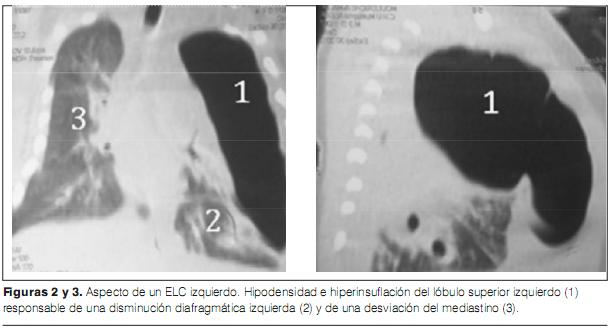

Lobar holoprosencephaly | Radiology Case | Radiopaedia.org  Congenital lobar emphysema | Eurorad

Congenital lobar emphysema | Eurorad  Lobar collapse demystified: the chest radiograph with CT correlation | Postgraduate Medical Journal

Lobar hemorrhage | Radiology Reference Article | Radiopaedia.org  Congenital Lobar Emphysema - The Clinical Advisor

Congenital Lobar Emphysema - The Clinical Advisor  Lobar Holoprosencephaly in 2020 | Retroverted uterus, Cleft lip and palate, Cleft lip

ENFISEMA LOBAR CONGENITO PDF  Lobar holoprosencephaly | Radiology Case | Radiopaedia.org

Congenital lobar overinflation | Radiology Reference Article | Radiopaedia.org  CONGENITAL LOBAR EMPHYSEMA | buyxraysonline

CONGENITAL LOBAR EMPHYSEMA | buyxraysonline  ENFISEMA LOBAR CONGENITO PDF

ENFISEMA LOBAR CONGENITO PDF  Lobar holoprosencephaly | Radiology Case | Radiopaedia.org

39 Congenital Lobar Emphysema | Radiology Key  Right upper lobe consolidation: an unusual complication of an uneventful endotracheal intubation

ENFISEMA LOBAR CONGENITO PDF  (PDF) Stereotactic Cortical Atlas of the Domestic Canine Brain

Congenital lobar emphysema | Eurorad  Home - Lobar Incorporated

ENFISEMA LOBAR CONGENITO PDF  A case of lobar holoprosencephaly in neonatus one-month old who | Download Scientific Diagram

Congenital Lobar Emphysema Article  PPT - Chest X-Ray Interpretation for the Internist PowerPoint Presentation - ID:934924

Congenital Lobar Emphysema - Metabolic Disorders - My Fertility Guide  Congenital Lobar Emphysema | Thoracic Key

Congenital Lobar Emphysema | Thoracic Key  a CT showing large lobar hemorrhage at the left parietal lobe. b A | Download Scientific Diagram

Congenital lobar emphysema: diagnostic and therapeutic challenges | BMJ Case Reports  Lobar hemorrhage | MedLink Neurology